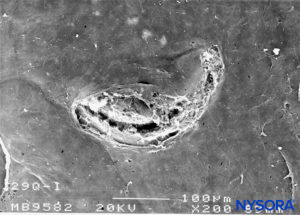

FIGURE 24. Dura-arachnoid lesion produced with 22-G Quincke needle. Arachnoid surface. Scanning electron microscopy. Magnification ×100. (Reproduced with permission from Raj P: Textbook of Regional Anesthesia. Philadelphia: Churchill Livingstone; 2002.)

Piercing the dural sac during a subarachnoid block causes mechanical disruption of both the dura mater and the arachnoid layer. The cross-sectional area of the puncture site produced by a 25-gauge needle is similar regardless of whether the needle has a pencil point or a cutting end. However, the morphology of the lesion varies depending on the design of the needle tip. Pencil-point needles produce a greater and rougher-appearing injury to the dural fibers, while cutting needles produce a U-shaped lesion or flap resembling the open lid of a tin can (Figures 8 to 31).

When using cutting (long bevel) needles, bevel orientation (eg, parallel or perpendicular to the main axis of the cord) does not significantly affect the size or morphology of the lesions in the dura and arachnoid lamina (see Figure 24). The lesion that the needle produces in the dural sac has two components, dural and arachnoid. It is believed that the arachnoid component is vital in limiting cerebrospinal fluid leakage from the subarachnoid space to the epidural space. Therefore, the size and morphology of arachnoid lesions seem to be more important for laminar sealing and cerebrospinal leakage than the size and morphology of dural lacerations.

The incidence of postdural puncture headache (PDPH) has been thought that is affected by the type of needle used (pencil point versus cutting) and of the bevel. The traditional belief that cutting needles result in larger dural lesions (tears) was established in the 1940s and may have been the consequence of the imperfections in the needle design of that era. Modern needles, however, produce clean, U-shaped lesion or flap resembling the open lid of a tin can (see Figure 24).

After needle withdrawal, the U-shaped flap tends to return to its original position due to cerebrospinal fluid pressure and the elastic properties of the dura mater. The dural orifice is almost completely occluded after approximately 15 minutes. On the other hand, lesions produced by pencil-point needles involve a more complex lesion with fiber tearing, sectioning, and separation. The extent of the dural lesion caused by a needle depends on several factors, including the external diameter of the needle, dural and arachnoid sealing mechanisms, needle-tip design, and the quality of needle manufacturing. Needles having the same tip design but different manufacturing methods may not have the same surface quality and may contain microfractures or imperfections, resulting in more or less extensive dural fiber tearing and residual lesions.